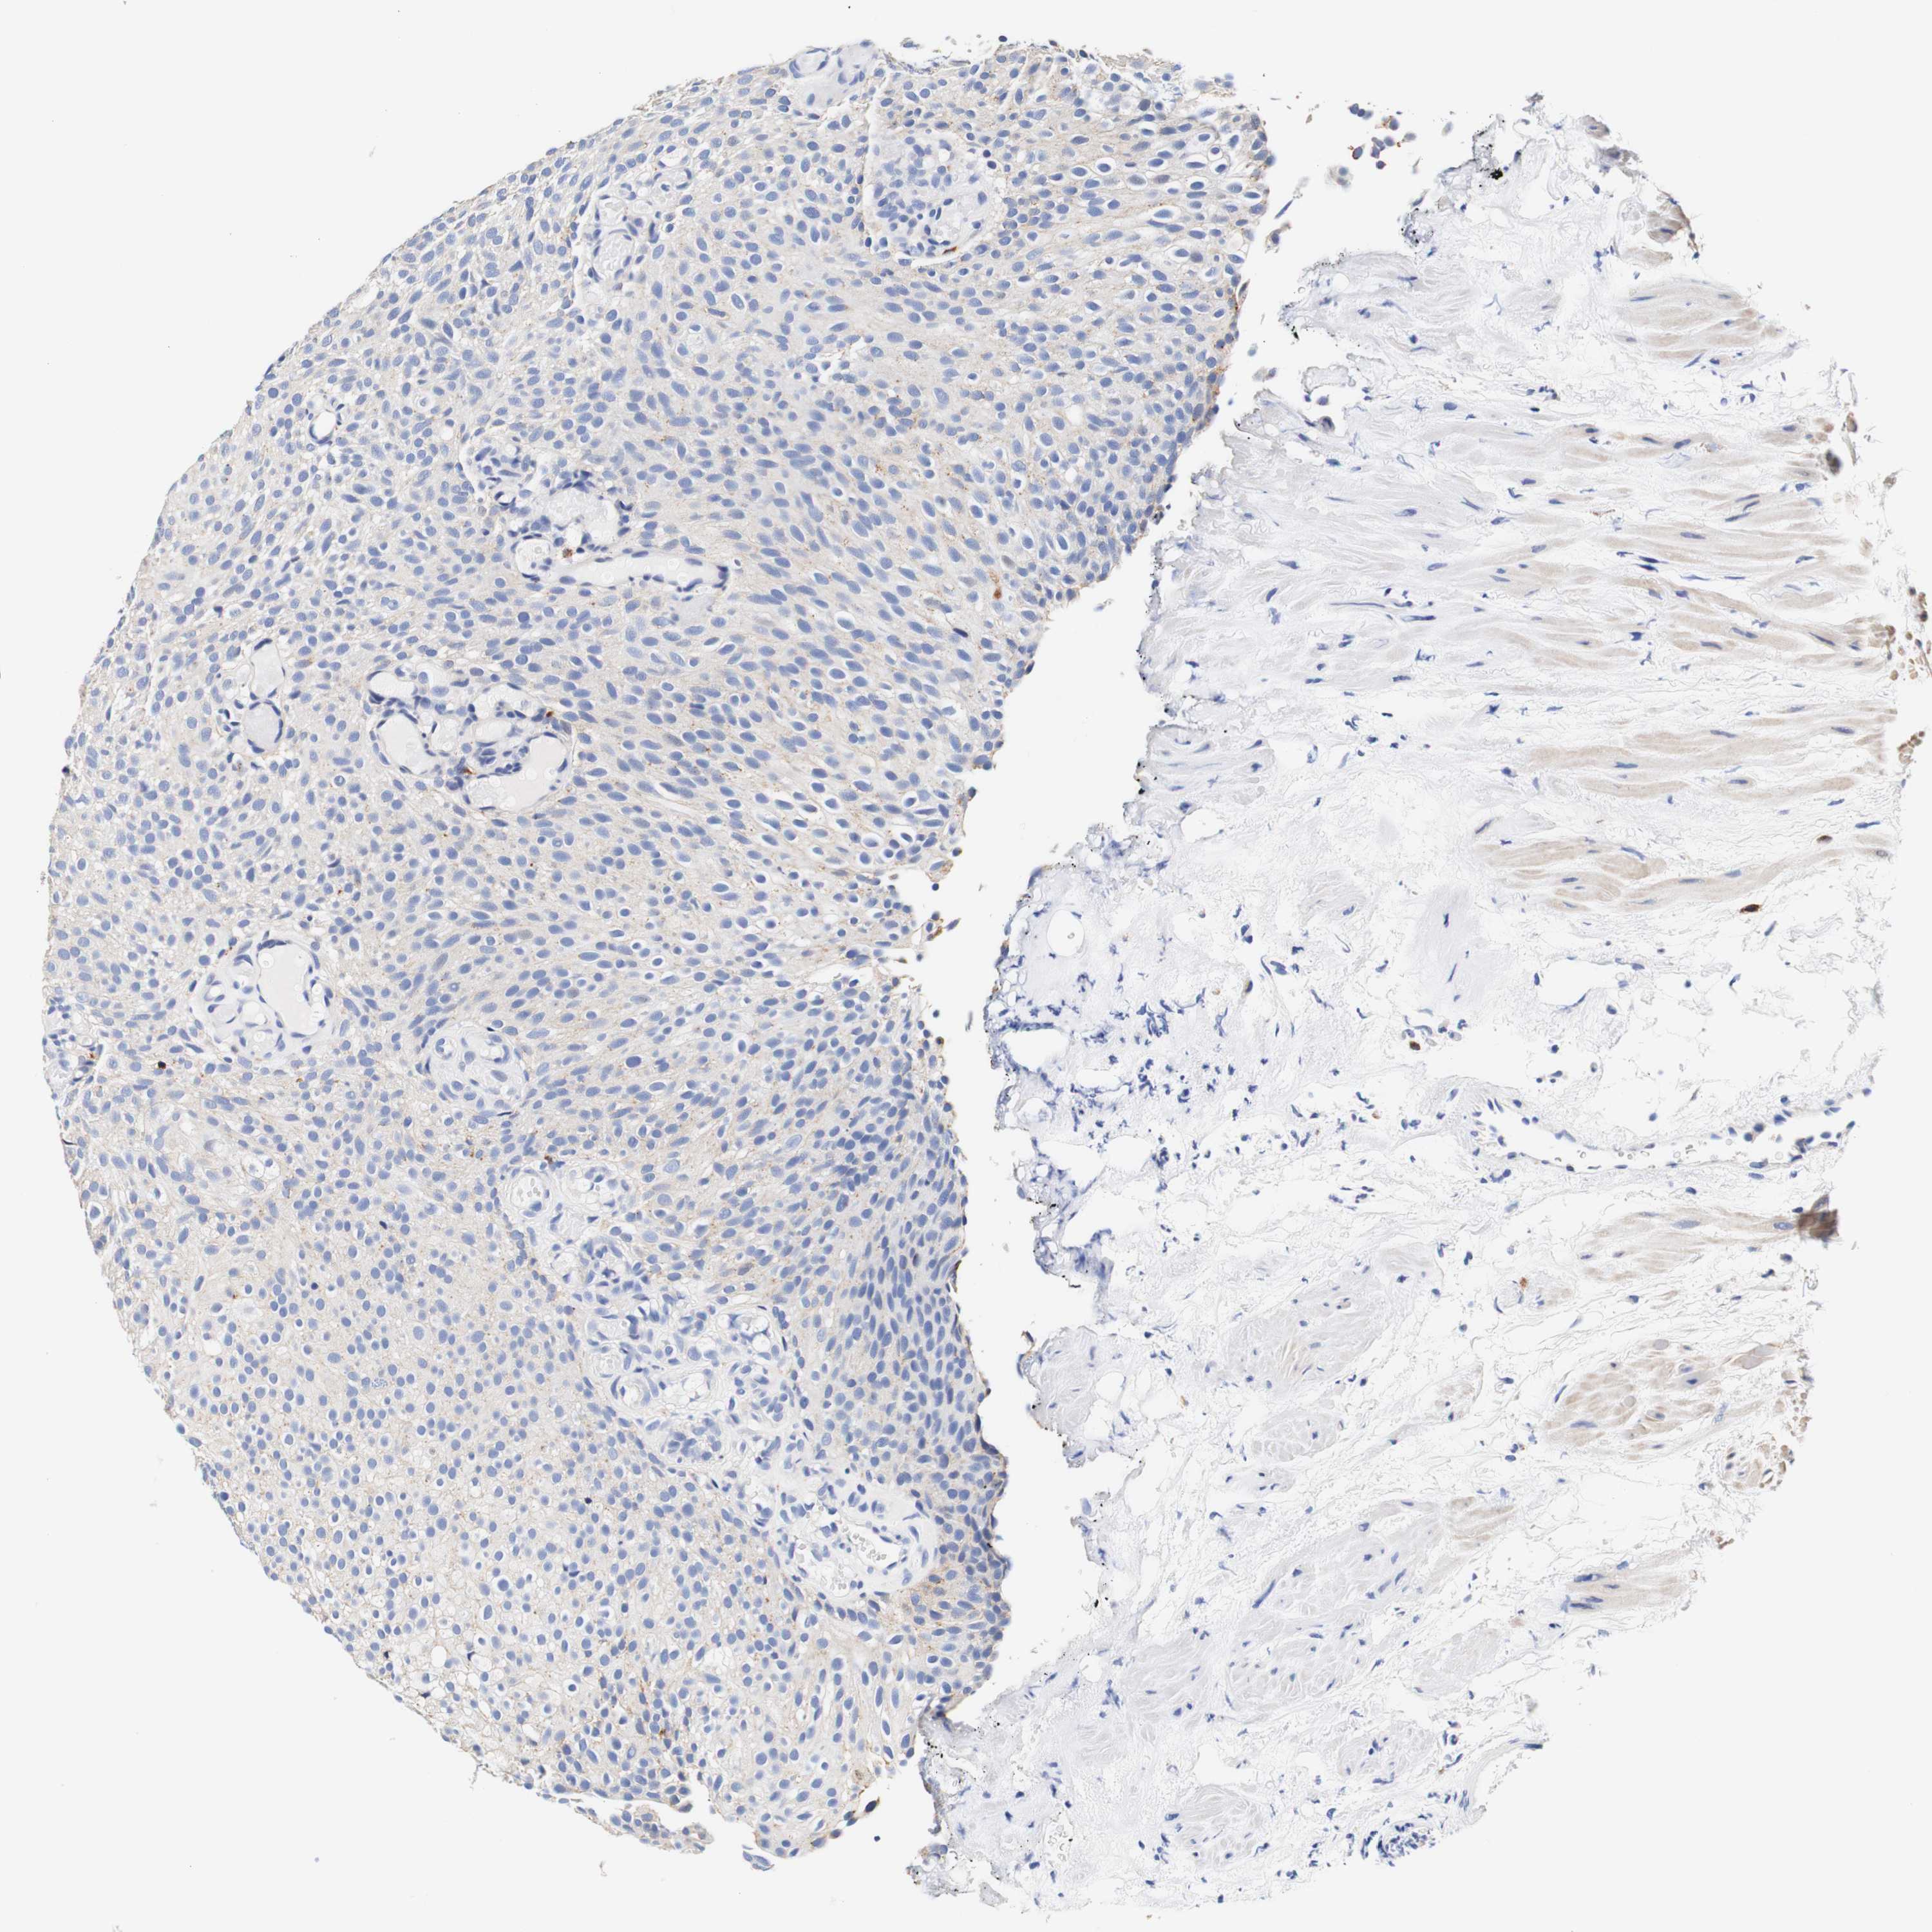

UROTHELIAL CANCER - Protein expressioni

A mouse-over function shows sample information and annotation data. Click on an image to view it in a full screen mode. Samples can be filtered based on level of antibody staining by selecting one or several of the following categories: high, medium, low and not detected. The assay and annotation is described here.

Note that samples used for immunohistochemistry by the Human Protein Atlas do not correspond to samples in the TCGA dataset.

Antibody stainingi

Antibody staining in the annotated cell types in the current human tissue is reported as not detected, low, medium, or high, based on conventional immunohistochemistry profiling in selected tissues. This score is based on the combination of the staining intensity and fraction of stained cells.

Each image is clickable and will lead to virtual microscopy that enables deeper exploration of all samples and also displays staining intensity scores, fraction scores and subcellular localization as well as patient and tissue information for each sample.

Antibody HPA011753

Antibody HPA017206

Antibody CAB004347

Staining

High

Medium

Low

Not detected

Intensity

Strong

Moderate

Weak

Negative

Quantity

>75%

75%-25%

<25%

None

Location

Nuclear

Cytoplasmic/membranous

Cytoplasmic/membranous,nuclear

Urothelial carcinoma, Low grade

Urothelial carcinoma, High grade